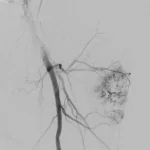

65 year old with a left femoral renal metastasis lesion. Angiograms showing vascularity of the lesion. The two annotated images show the tortuosity of the vessel supplying the lesion. The dotted orange coloured line shows the path of the vessel. It was not possible to cannulate this artery with conventional microcatheters.